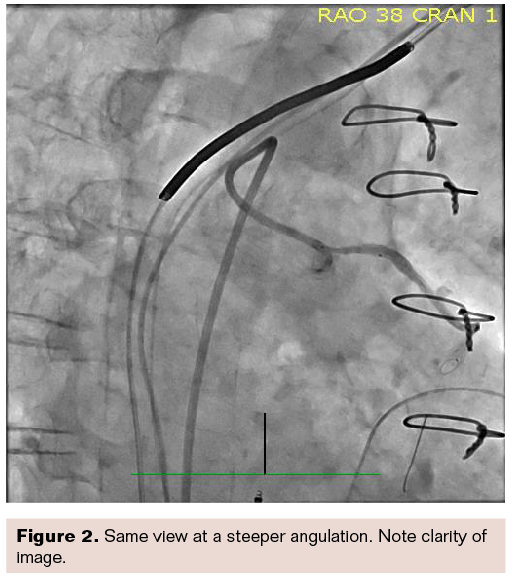

We were able to intervene on that vein graft using relatively shallow angles and of course would expect the views to be clear, because the imaging does not require penetrating a lot of tissue. Figure 1 is the diagnostic injection. Figure 2 is the same right anterior oblique (RAO) view, but steeper and more angulated at a 38-degree angle. Note the image is still quite clear in this fairly obese person, with image quality almost identical between the two views shown in Figures 1-2.